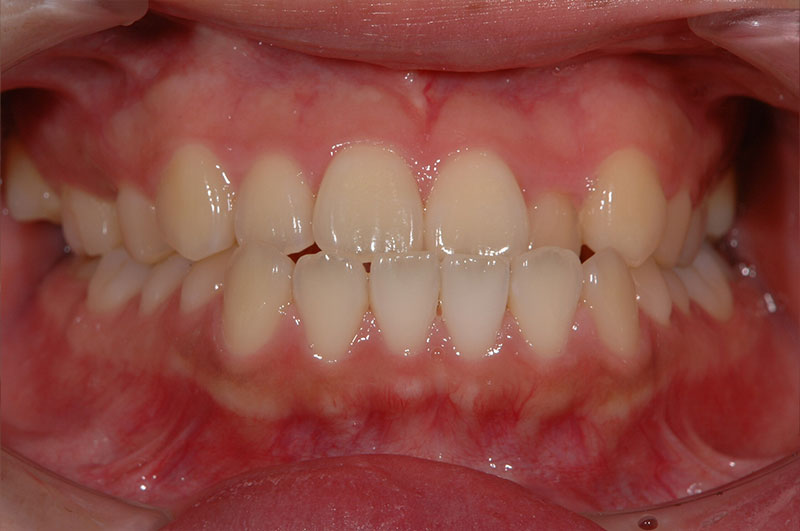

今回は反対咬合に対して、外科手術を行わずに矯正治療のみで改善した成人の症例をご紹介します。

「反対咬合=手術が必要」と思われがちですが、噛み合わせの状態によっては、今回のように矯正治療だけで改善が可能なケースもあります。

治療前後の変化を実際の症例写真でご覧いただくことで、

反対咬合がどのように改善するのかを、イメージしていただければと思います。

症例の概要(手術なし・成人の反対咬合)

術前

術後

| 主訴 | 反対咬合 |

| 初診時年齢 | 24歳 |

| 治療内容・使用した装置 | 頬側ブラケットを用いた永久歯全体の矯正治療、アンカースクリュー |

| 抜歯の有無 | 左右下顎第一小臼歯、左側上顎第二小臼歯抜歯 |

| 治療期間 | 約24ヶ月 |

| 費用 | 総額819,500円(税込) (相談料、検査料、診断料、動的治療費、抜歯費、アンカースクリュー埋入、除去費、保定期間料等含む) |

| 治療に伴うリスク・副作用 | 歯の移動に伴う痛み、上下顎前部の歯根吸収、装置による口内炎、ブラッシング不良によるむし歯、歯周炎 |